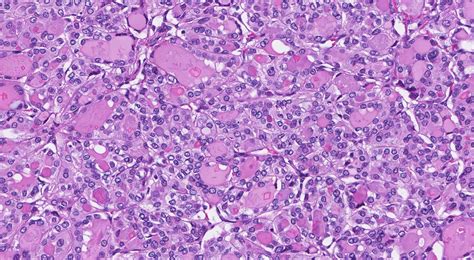

Fine Needle Aspiration (FNA) A thin needle is used to extract a small sample of cells from the nodule for laboratory analysis.